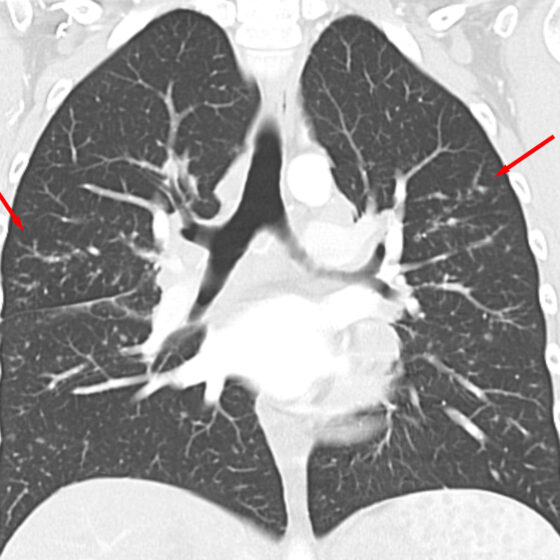

• This content is machine translated Sarcoidosis: una enfermedad multisistémica

La biopsia es una pieza importante del rompecabezas

La sarcoidosis puede aparecer a cualquier edad y suele afectar a los pulmones, pero también pueden verse implicados otros órganos. El diagnóstico consta de varios pasos, no existen análisis de…

• This content is machine translated Diagnóstico y terapia de la sarcoidosis

Enfermedad pulmonar que también afecta al reumatólogo

La sarcoidosis afecta más comúnmente a los pulmones, pero también se producen manifestaciones extrapulmonares. La afectación aislada de un solo órgano o sistema orgánico es rara en la sarcoidosis, por…

• This content is machine translated Enfermedad pulmonar intersticial

La cortisona como cura milagrosa relativa

Las enfermedades pulmonares intersticiales son frecuentes en la consulta de los médicos de familia, sobre todo en sus formas iniciales. La diferenciación entre las distintas formas no suele ser evidente…